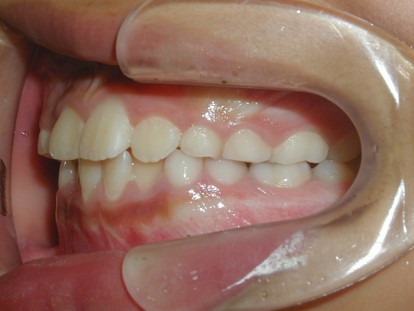

永久歯に交換するためのスペース不足による前歯のガタガタで、取り外しができる拡大床にて上下顎の幅を拡大した後、上顎の前歯をマルチブラケット装置で並べました。治療の期間は1年9か月でした。

初診時

終了時